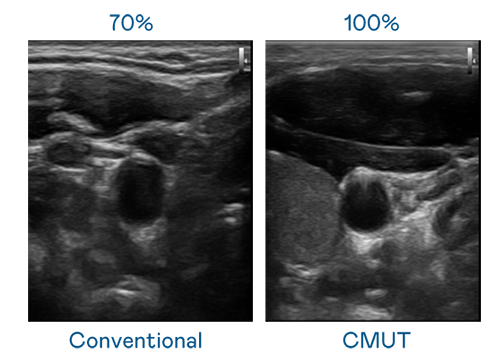

CMUT 技術是一種用電容式微機電元件來產生超音波訊號的技術。與傳統 PZT 壓電式技術相比,CMUT 頻寬增加 30%,更寬頻的超音波訊號讓影像解析度大幅提升,是實現高影像品質醫療超音波掃描、促進精準醫療發展的關鍵技術。

超音波影像的解析度高低,首先取決於探頭能發出的訊號頻寬。z6mg人生就是博 CMUT 可提供高清晰的超音波訊號,提供高頻寬、高靈敏度、影像紋理細節更高的超音波影像,協助醫護人員縮短影像判讀時間及利用精準的醫療影像進行診斷。